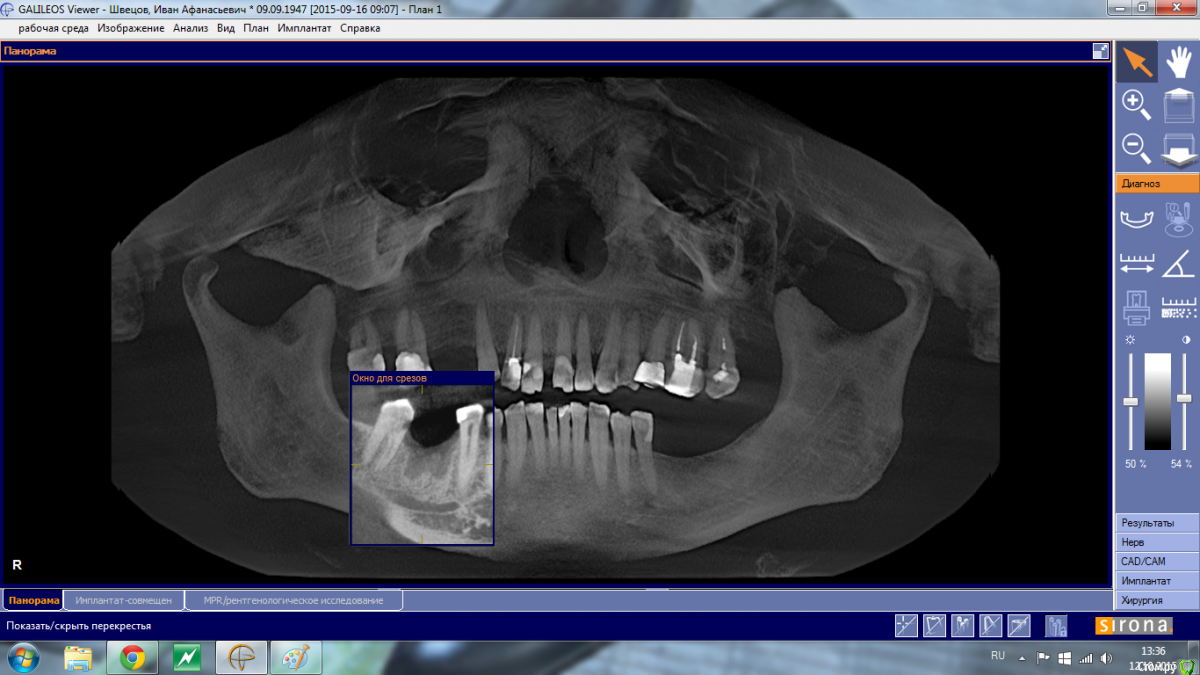

Shakirbura Опубликовано 12 октября, 2015 Автор Поделиться Опубликовано 12 октября, 2015 Снимок до имплантации.Сверло уперлось в 8-9 мм, что для меня было неожиданностью Ссылка на комментарий

АнтонТЛТ Опубликовано 13 октября, 2015 Поделиться Опубликовано 13 октября, 2015 Снимок до имплантации.Сверло уперлось в 8-9 мм, что для меня было неожиданностьюСкорее всего уперлись в подъязычное поднутрение, резцы с парестезией? 2 Ссылка на комментарий

АнтонТЛТ Опубликовано 13 октября, 2015 Поделиться Опубликовано 13 октября, 2015 Давайте контрольный снимок, если имплантат далеко от канала, то скорее всего травма + гематома (само пройдет), если имплантат в канале, то вынимать. 3 Ссылка на комментарий

Доктор Дмитрий Опубликовано 13 октября, 2015 Поделиться Опубликовано 13 октября, 2015 Рисковый доктор, куча сомнений и без контроля. Ни прицельного, ни панарамника, ни кт, я бы уже точно пац вызвал на снимок Ссылка на комментарий